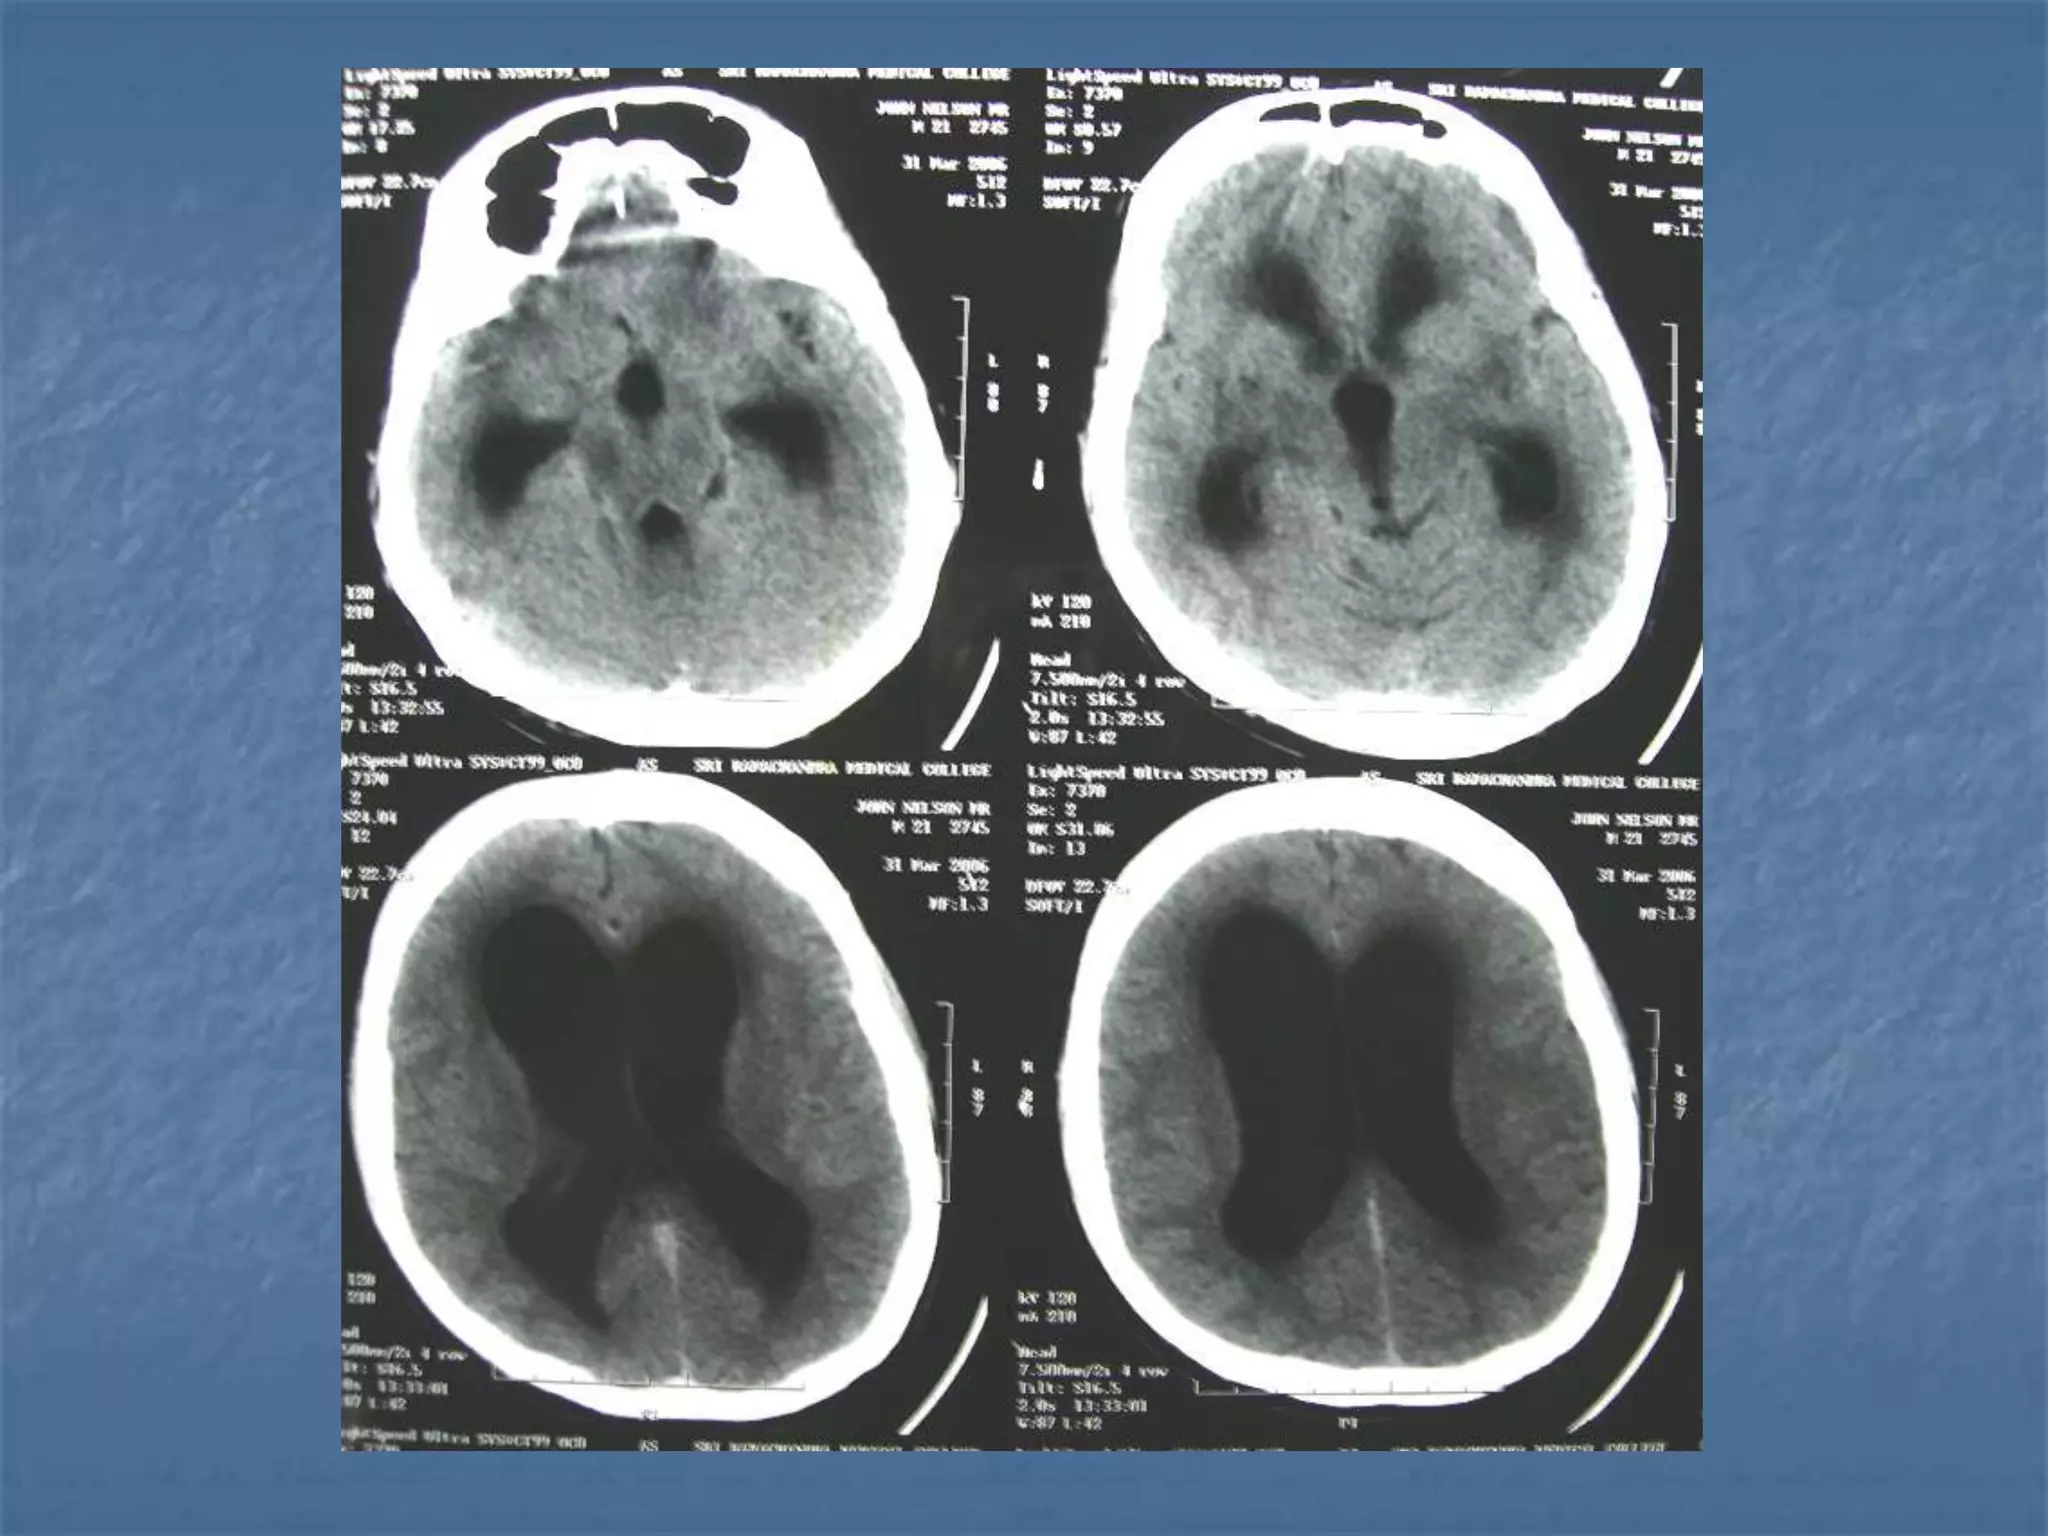

Ventriculitis / Ependymitis

 Inflammation and enlargement of the

ventricles characterizes ventriculitis.

Ependymitis shows hydrocephalus with

damage to the ependymal lining and

proliferation of subependymal glia. A CT of

patients with these conditions reveals the

presence of periventricular edema and

subependymal enhancement. Ventriculitis and

Ependymitis affect approximately 30% of the

adult patients and 90% of the pediatric

patients with meningitis.